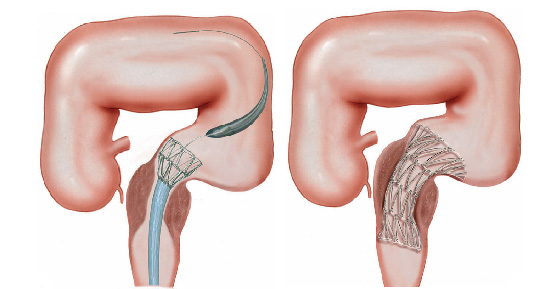

O que é o piloro ?

Piloro é o esfíncter que fica na poção final do estômago, na sua transição com o duodeno. Com os movimentos de contração do estômago o piloro se abre a permite que o conteúdo estomacal passe para o duodeno.

Estenose de piloro

Estenose do piloro é o estreitamento parcial ou total do mesmo que impede a progressão do conteúdo do estômago para o duodeno.

Estenose do piloro pode acontecer por 3 causas principais:

1- Estenose hipertrófica do piloro: condição que acontece em alguns recém nascidos onde o musculo do esfíncter fica muito “apertado” e impede que o conteúdo estomacal passe para o intestino. Nestas casos as crianças tem crises de vômitos e ficam desnutridas. A resolução deste problema é feita por cirurgia através do procedimento de piloroplastia.

2- Tumores do estômago: alguns tumores do estômago podem crescer ao ponto de causar a obstrução do piloro impedindo a progressão do conteúdo estomacal. Nestes casos geralmente realiza-se cirurgia para se retirar a parte do estômago acometida. Nos casos muito avançados pode-se passar através de endoscopia uma prótese autoexpansível para desobstrução.

Alguns casos onde a colocação da prótese não é possível realiza-se o procedimento de derivação gástrica, ligando o estômago com o intestino.

3- Estenose benignas: algumas úlceras do estômago ou do piloro podem ao cicatrizar levar a retração da parede do órgão e fechamento do piloro. Nestes casos realiza-se a dilatação endoscópica da região com balão do tipo hidrostático.

Nos casos onde não há melhora com as dilatações realiza-se o tratamento cirúrgico do problema.